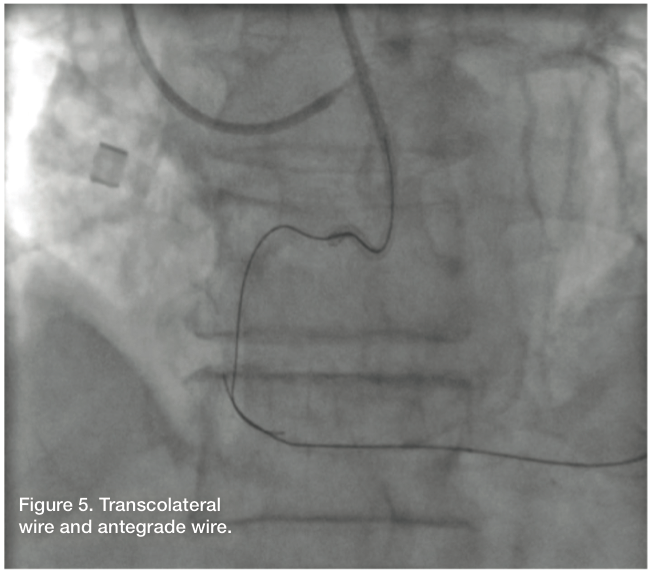

Using a Fielder wire and a 1.25mm balloon, we attempted to cross through the septal. However, we could not find an adequate collateral via selective injection of the septal. We then went back to the circumflex artery using a Pilot wire and a 1.25mm Sprinter balloon (Medtronic). Initial attempts were unsuccessful; however, after selective injection through the balloon, an ideal channel was located and successfully navigated. In an attempt to advance the balloon, the guide and guidewire popped out, secondary to poor guide support. We were able to recross into the distal posterior descending artery (PDA). This was confirmed by selective angiogram after advancing the 1.25mm balloon through the collateral into the distal RCA. We exchanged for a Miracle Bros wire and tried to navigate the RCA in retrograde fashion. This was unsuccessful. We then took a Pilot wire, and with the Pilot 200, we were able to navigate the RCA in retrograde fashion. We snared the wire and externalized it in the right radial artery. This did result in fracture of the distal wire tip while trying to externalize it. However, the fracture took place in the right radial sheath and was easily managed.